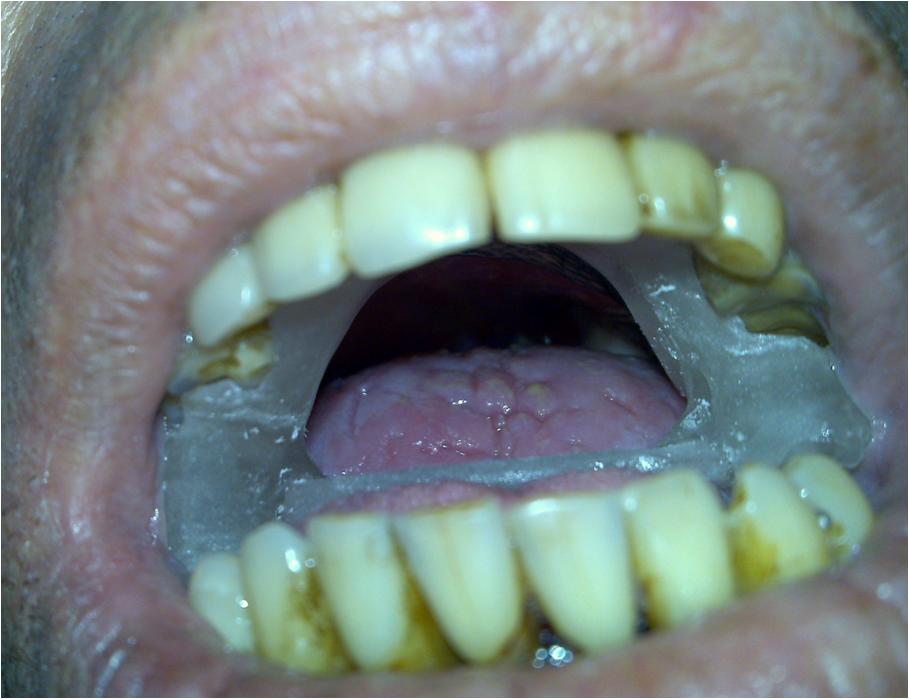

O carcinoma epidermoide de palato mole (CEPM) é uma neoplasia de baixa prevalência que representa a minoria dos tumores que podem acometer a orofaringe. Quando diagnosticados em estádios iniciais, as opções de radioterapia ou cirurgia são aventadas para abordagem terapêutica com taxas de controle locorregional e sobrevida semelhantes. Este estudo tem como objetivo: relatar o caso de um paciente encaminhado ao Departamento de Radioterapia do Centro de Oncologia do Hospital Sírio-Libanês com diagnóstico de CEPM e tratado de forma curativa com radioterapia (teleterapia com técnica de modulação de intensidade de feixe e braquiterapia de altas doses com irídio -192).